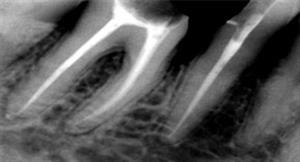

Root Canal Treatment

Before

A root canal procedure (endodontic treatment) is often required to save an infected tooth. Bacteria can enter a tooth through a cavity or a damaged filling. When this happens, the tooth can become abscessed, meaning the pulp inside the tooth becomes infected. An abscessed tooth can be quite painful and cause swelling in the surrounding gum tissues. If left untreated, it can cause several oral health problems. A root canal procedure removes the infected pulp and any other infected tissues within the tooth.